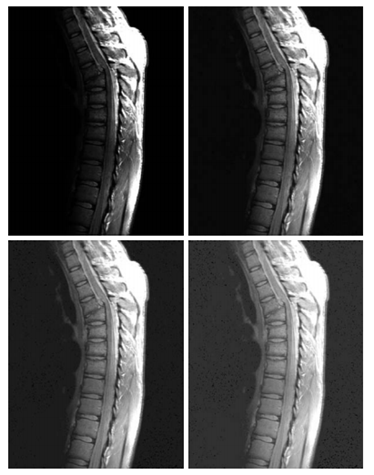

下面我们看几个使用指数变换进行对比度增强的例子。

压缩高亮度区域,将低亮度区域展现得更加清晰。

上图中从左到右,从上到下依次为:人体脊椎的核磁共振图像,经过指数变换 之后的图像,经过指数变换

之后的图像,经过指数变换

之后的图像。从中可以看出,低亮度区域展现得越来越明显。